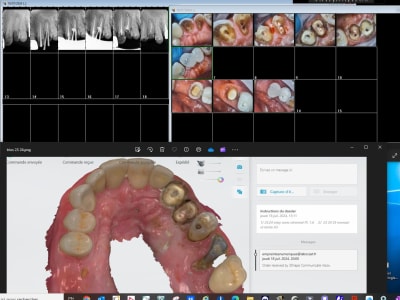

Inlay core+ ccm 13 23 33 + stellites haut et bas. J' ai du faire un essayage pour augmenter la dv.

Empreinte/essayage prise rim avec augmentation de dv/ pose.

Zéro retouche, le patient a annulé le rdv de contrôle a une semaine car c'est parfait

Je te laisse admirer l'occlusion.